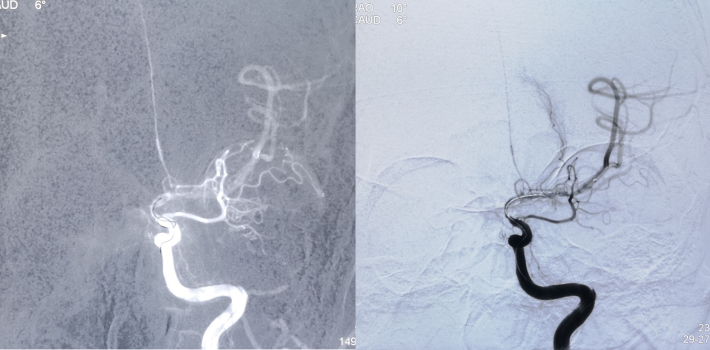

球囊扩张后

4.5mm*22mm Enterprise 支架

术 后

✔支架选择:左侧颈内动脉虹吸段狭窄段长度较长,远端至左侧大脑中动脉M1起始段,近端至眼动脉开口上方。且此段血管迂曲,狭窄段近端、远端都有较大的血管转折,使用球扩支架风险很高。因此我们选用了顺应性较好,又有一定支撑力的自膨支架——Enterprise 支架。

✔术中要点:左侧颈内动脉虹吸段狭窄考虑为夹层,予反复多个角度导引导管造影,以明确真假血管腔,微导丝通过狭窄段血管时谨慎、轻柔操作,务必判断导丝应从真腔通过。先予球囊扩张,观察扩张后狭窄段血管管径恢复情况。释放前准确定位支架近端,远端,应完全覆盖狭窄血管段。